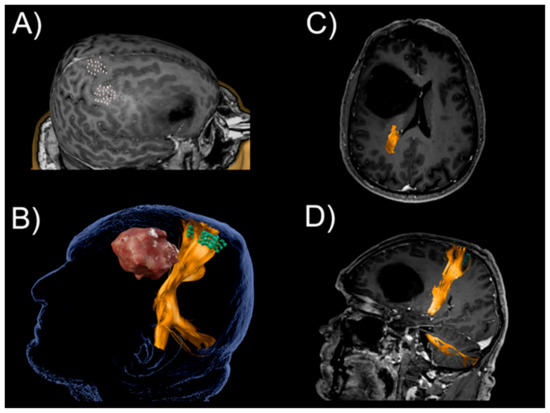

2.2. Fiber Tractography

- Krieg, S.M.; Buchmann, N.H.; Gempt, J.; Shiban, E.; Meyer, B.; Ringel, F. Diffusion tensor imaging fiber tracking using navigated brain stimulation—A feasibility study. Acta Neurochir. 2012, 154, 555–563. [Google Scholar] [CrossRef] [PubMed]

- Frey, D.; Strack, V.; Wiener, E.; Jussen, D.; Vajkoczy, P.; Picht, T. A new approach for corticospinal tract reconstruction based on navigated transcranial stimulation and standardized fractional anisotropy values. NeuroImage 2012, 62, 1600–1609. [Google Scholar] [CrossRef] [PubMed]

- Conti, A.; Raffa, G.; Granata, F.; Rizzo, V.; Germano, A.; Tomasello, F. Navigated transcranial magnetic stimulation for “somatotopic” tractography of the corticospinal tract. Neurosurgery 2014, 10 (Suppl. 4), 542–554. [Google Scholar] [CrossRef] [PubMed]

- Weiss, C.; Tursunova, I.; Neuschmelting, V.; Lockau, H.; Nettekoven, C.; Oros-Peusquens, A.M.; Stoffels, G.; Rehme, A.K.; Faymonville, A.M.; Shah, N.J.; et al. Improved nTMS- and DTI-derived CST tractography through anatomical ROI seeding on anterior pontine level compared to internal capsule. NeuroImage. Clin. 2015, 7, 424–437. [Google Scholar] [CrossRef]

- Weiss Lucas, C.; Tursunova, I.; Neuschmelting, V.; Nettekoven, C.; Oros-Peusquens, A.M.; Stoffels, G.; Faymonville, A.M.; Jon, S.N.; Langen, K.J.; Lockau, H.; et al. Functional MRI vs. navigated TMS to optimize M1 seed volume delineation for DTI tractography. A prospective study in patients with brain tumours adjacent to the corticospinal tract. NeuroImage. Clin. 2017, 13, 297–309. [Google Scholar] [CrossRef] [PubMed]